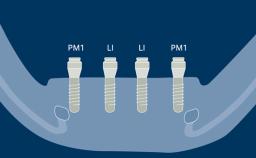

- identify strategic placement positions for implants in Kennedy Class I, II, and IV partial RDP designs